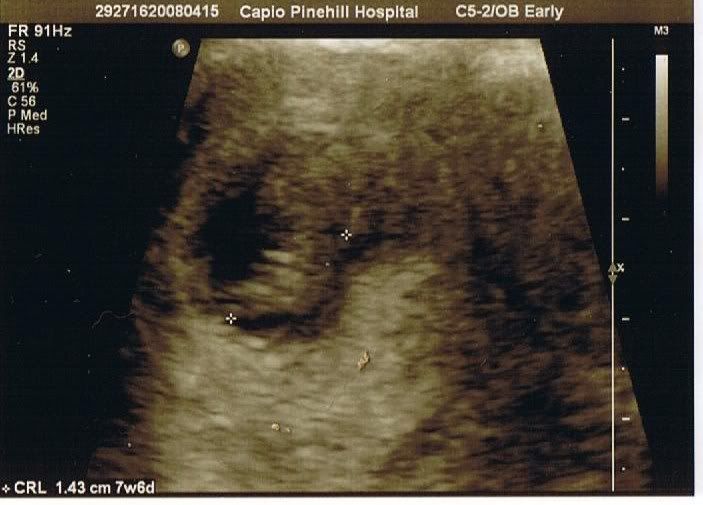

here's the scan pic

I'm kind of wondering if little 'orlando' is only 1.43cm why the hell none of my flippin clothes fit. it was so sweet to hear the little teeny heart beat though, amazing really eh.:A

After 2 kids & umpteen scans (we had loads in the olden days of 20+yrs ago!) I still can't work them out! How many weeks are you, Toto?